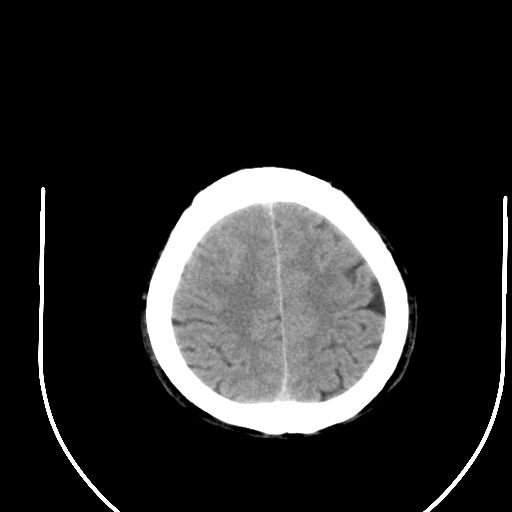

标题: CT24997:M,60Y,突发昏迷30分钟,有高血压病史。 [打印本页]

标题: CT24997:M,60Y,突发昏迷30分钟,有高血压病史。

右侧基底节区脑出血并破溃入脑室。

支持楼主诊断,脑中线结构有偏移,脑疝形成可能!